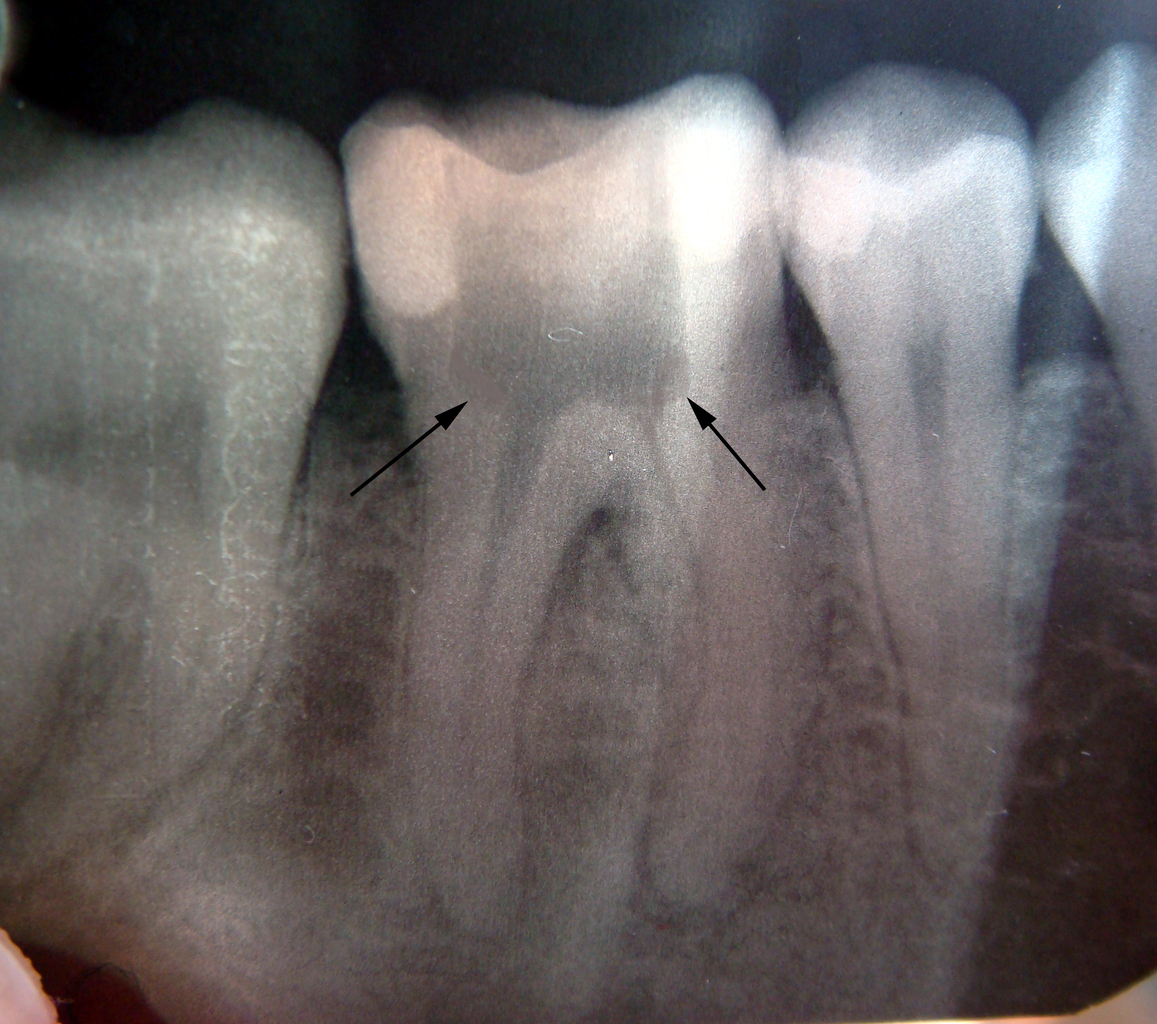

Рентгеновские снимки кариеса корня зуба

Раздел: Визуальные уроки